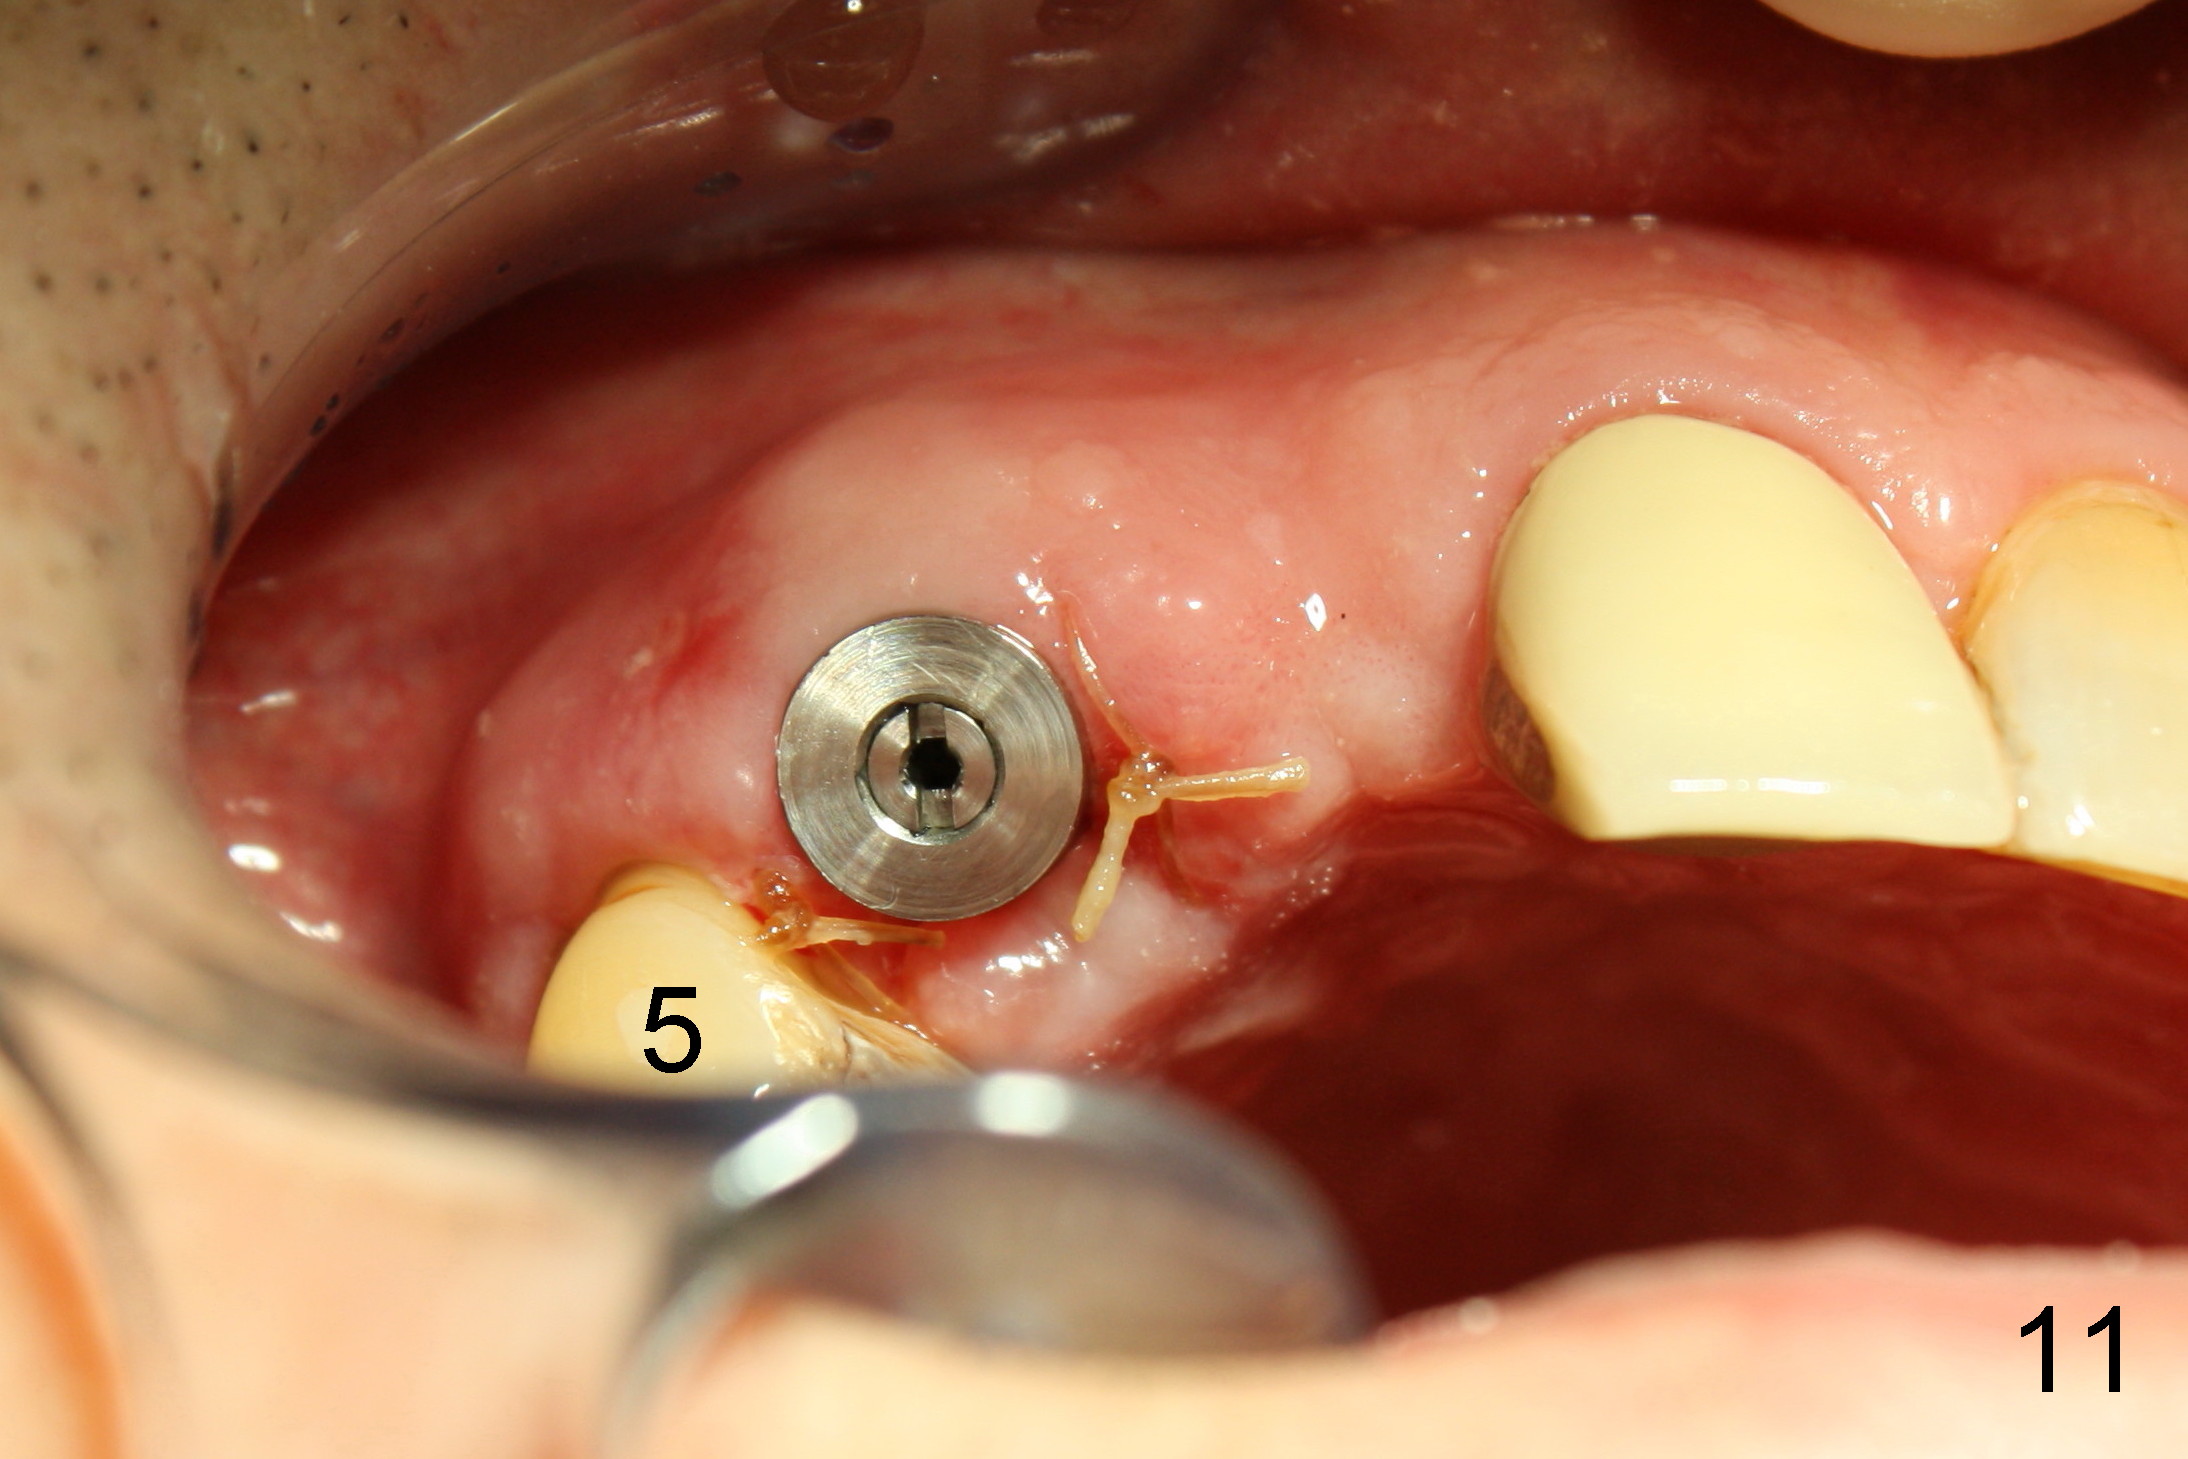

One week after #6 immediate implant placement, the patient is doing well. There is apparently enough clearance between the tooth #5 and the implant in term of bone (Fig.10, compare to Fig.4) and soft tissue (Fig.11, compare to Fig.3).